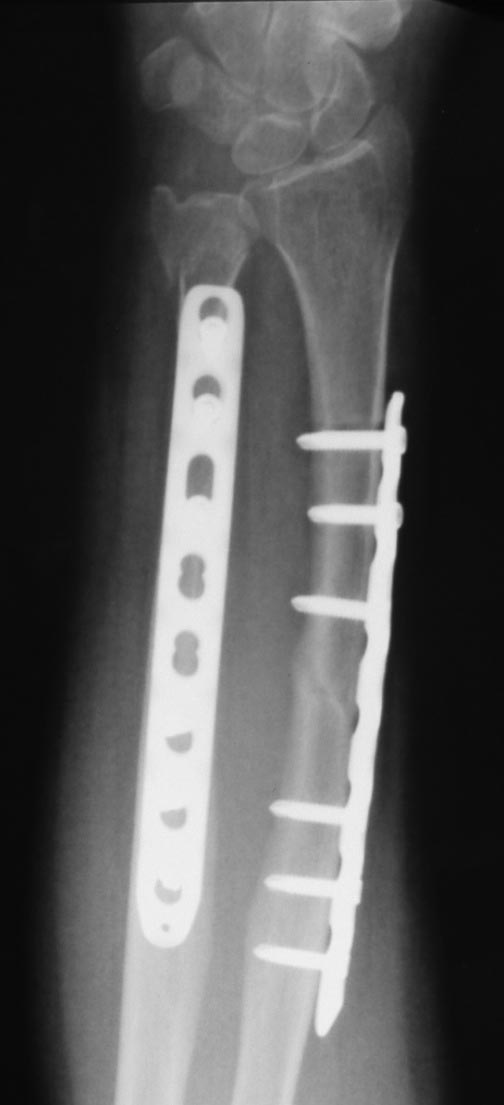

Уважаемые коллеги.Пациентка 45 лет прооперирована по поводу перелома костей предплечья 26.01.12. Послеоперационый период гладкий, функция предплечья восстановилась. 12.05.12 упала повторно (обморок). Диагностирован перелом головки локтевой кости. На мой взгляд, имеется и перелом по ходу дистального винта лучевой кости (появилось разрежение вокруг винта, которого не было на рентгенограммах через 1.5 мес. после операции). Хотя, локальной болезненности в этом месте нет. Болит в проекции кистевого сустава. Вопрос: показано ли удаление этого винта? Не будет ли он препятствовать консолидации?Заранее спасибо за ответы.

Может быть я не очень четко описал ситуацию или Вы невнимательно рассмотрели рентгенограммы. Первый снимок был сделан через полтора месяца после операции, 12 марта. Там еще прослеживается линия перелома. Но нет никаких признаков нестабильности. А 2 и 3-й снимки сделаны вчера, после нового падения пациентки. И на них прекрасно видно, что переломы, по поводу которых была сделана первичная операция, полностью срослись. Но появилось разрежение вокруг одного из винтов. Что и дает повод предполагать наличие перелома по ходу этого винта. И о каком переломе пластины при давно сросшемся переломе Вы говорите? А по поводу проблем с LCP в виде замедленного сращения: я уже лет 8-10 никакие другие пластины не ставлю. И этой пациентке поставил не из-за остеопороза, а потому-что это лучший, чем обычная пластина, способ фиксации. Нагрузка после операции на предплечье возможна сразу, никакие лонгеты не нужны. За все эти годы я не видел ни одного перелома титановой LCP. Вырваться из кости при развитии ложного сустава она может, но сломаться...

Возможно Вы правы. Видно на последних снимках, что шурупы не под 90 градусов из-за ротации и сложилось впечатление что потеряли угловую устойчивость при смятии перелома. Если перелом сросся и видна мозоль, а не смятие перелома, то думаю шуруп не помешает сращению нового перелома. Площадь шурупа по отношению к перелому относительно мала.

Даже если линия перелома идет к дистальному винту, то 2 других держат - бетон. Гипсовая лонгета 4-5 недель, винт не удалять.